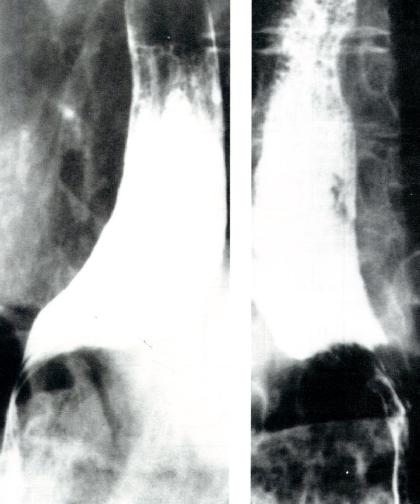

食管X线吞钡检查

DES患者可见非蠕动性同步收缩形成的节段性钡柱,称为“开塞钻食管”(图2.9)。钡透视亦可用于除外其他疾病的可能性。

图2.9 DES病人X线吞钡检查显示开塞钻食管。